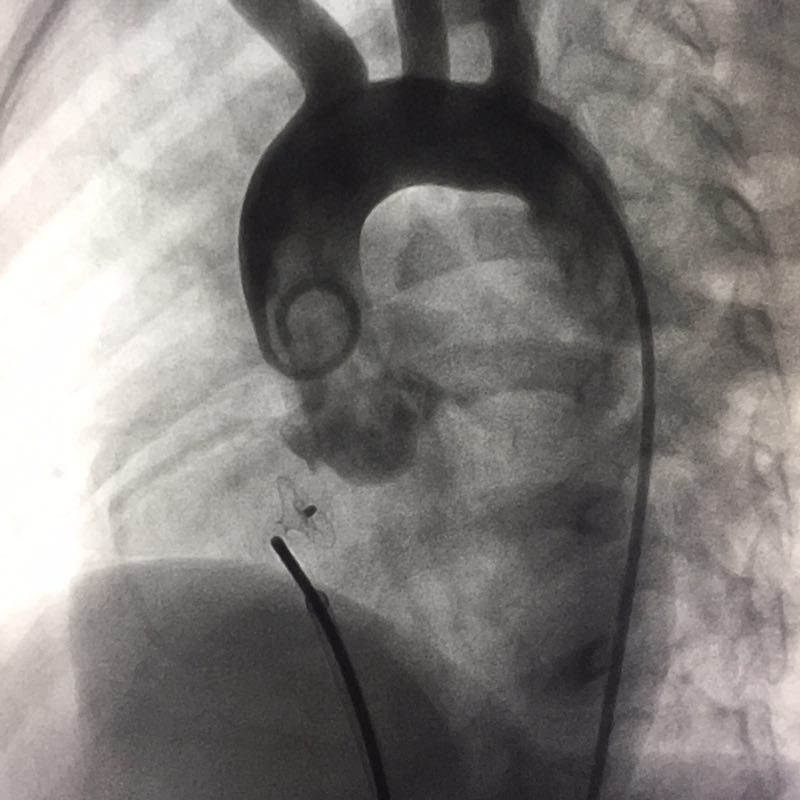

3月14日,张智伟主任向阿根廷专家演示了七台先天性心脏病介入手术,包括两台房间隔缺损封堵手术、三台室间隔缺损封堵手术和两台动脉导管未闭封堵手术。七台手术全部使用彩神在线网信彩票-彩神通免费版下载-彩神8争霸vlll-彩神购彩购彩大厅-彩神软件陆立根免费版-彩神ll争霸3-彩神ll彩神8-彩神ll争霸彩票-拼搏在线彩神网网页版科技公司自主研发的封堵器产品。其中一位先心病人情况较为复杂,为室间隔多孔缺损且缺损位置非常接近主动脉瓣。面对该挑战性病例张主任十分娴熟的将彩神在线网信彩票-彩神通免费版下载-彩神8争霸vlll-彩神购彩购彩大厅-彩神软件陆立根免费版-彩神ll争霸3-彩神ll彩神8-彩神ll争霸彩票-拼搏在线彩神网网页版科技室间隔封堵器植入病人缺损位置,并巧妙的避开了病人的主动脉瓣。术后造影显示,病人室间隔封堵完全,无残余分流。张主任精湛的医术和彩神在线网信彩票-彩神通免费版下载-彩神8争霸vlll-彩神购彩购彩大厅-彩神软件陆立根免费版-彩神ll争霸3-彩神ll彩神8-彩神ll争霸彩票-拼搏在线彩神网网页版科技产品卓越的性能是手术成功的重要保证,阿根廷医生一行对彩神在线网信彩票-彩神通免费版下载-彩神8争霸vlll-彩神购彩购彩大厅-彩神软件陆立根免费版-彩神ll争霸3-彩神ll彩神8-彩神ll争霸彩票-拼搏在线彩神网网页版科技公司产品在先心病治疗中的优势给予了高度评价。